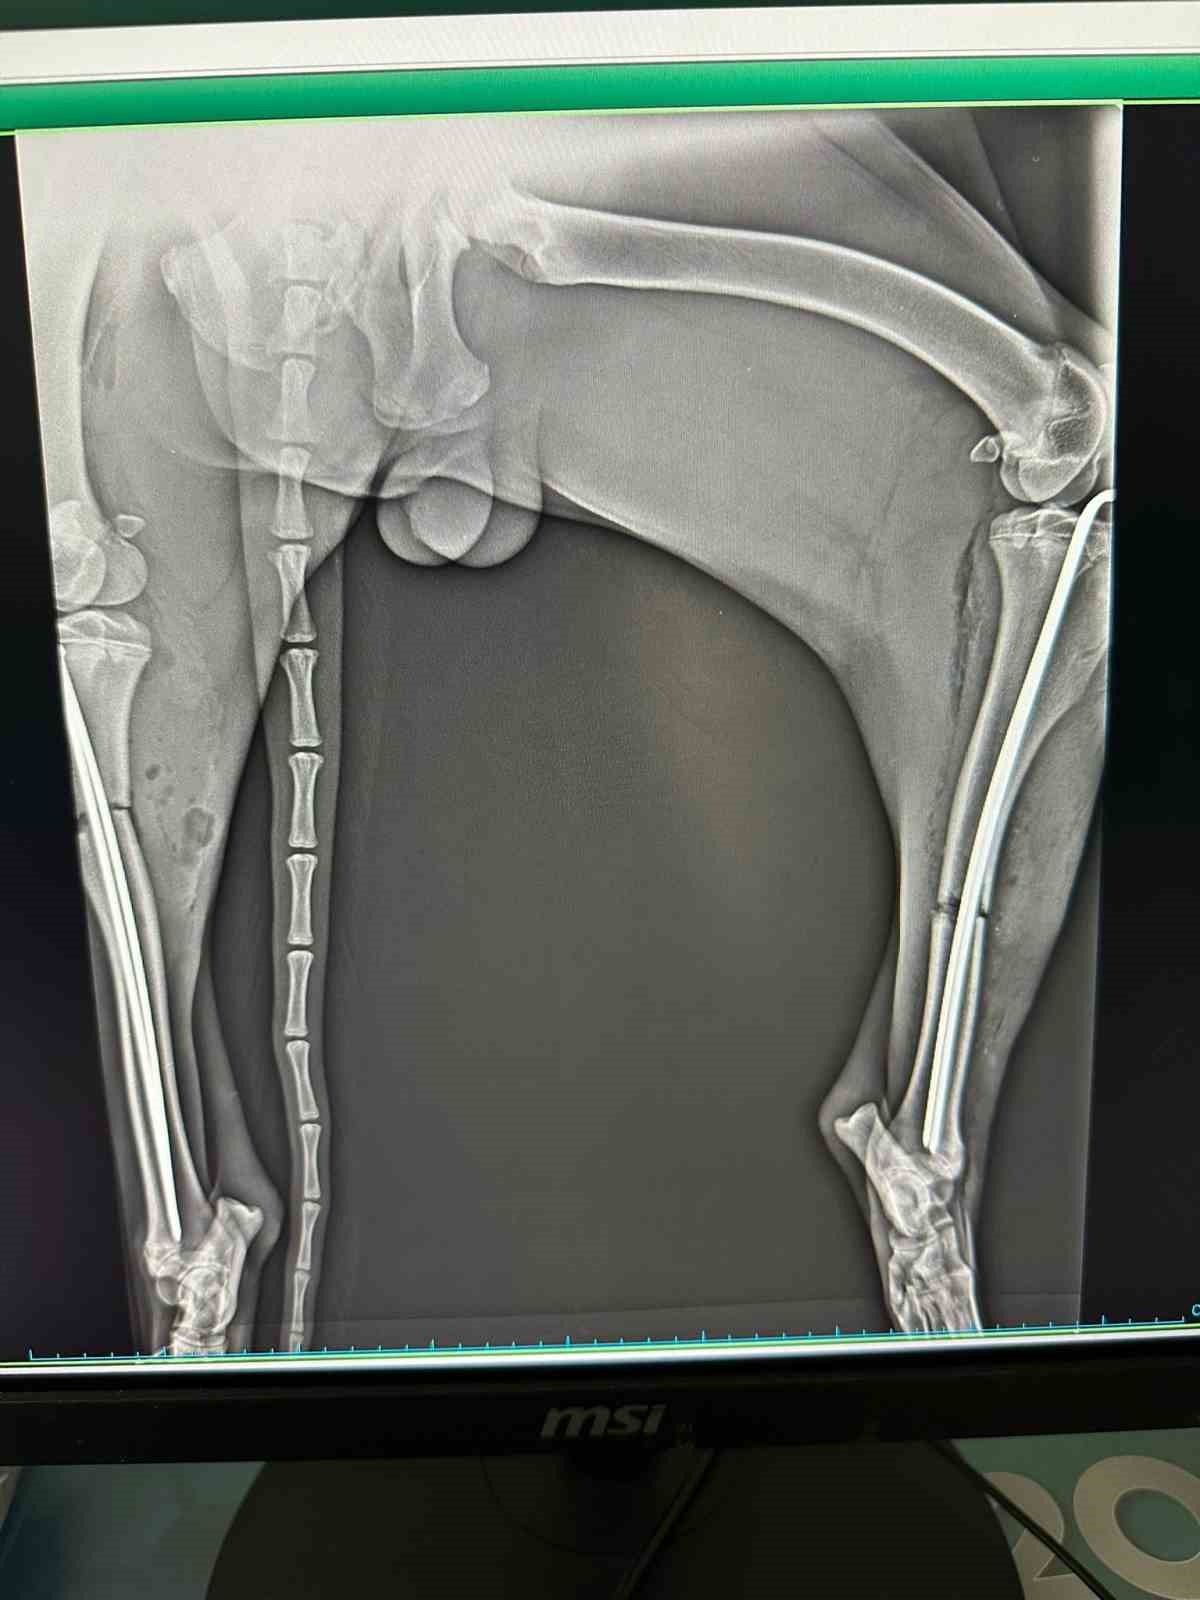

Veteriner hekimler tarafından köpeğe müdahale edildi. Yapılan tetkiklerde hayvanın sağ ve sol bacaklarında kırıklar olduğu belirlendi. Yaralı köpek, Osmaneli Belediyesi veteriner hekimi tarafından acil olarak ameliyata alındı. Başarılı geçen operasyonun ardından tedavi sürecine alınan köpeğin gözlem altında tutulduğu ve sağlık durumunun iyiye gittiği bildirildi. Yetkililer, tamamen iyileştikten sonra hayvanın doğal yaşam alanına bırakılacağını açıkladı.